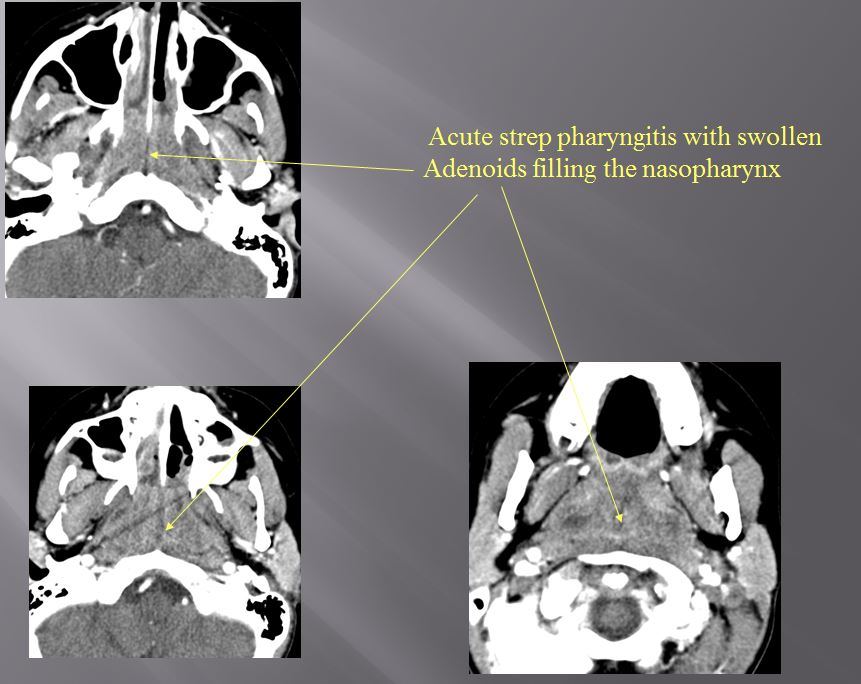

Nasopharynx

There is excessive enhancement or thickening of the mucosa or hypertrophy of the lymphoid tissue in the nasopharynx. [Yes/No]

There is evidence of an abscess within the lymphoid tissue of the nasopharynx. [Yes/No]

There is edema within the fat of the adjacent parapharyngeal space. [Yes/No]